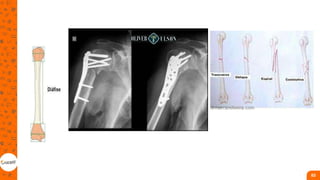

OMBRO

• Articulaçao mais móvel;

• Fratura proximal compromete

funcionalidade de todo membro;

• essas fraturas são causadas por

trauma direto, mas também, por

queda com a mão espalmada,

quedas de altura, acidentes

esportivos ou acidentes de

trânsito

1. hastes cefalomedulares - indicadas para as

fraturas transtrocantéricas e

subtrocantéricas;

2. placa e parafuso - indicados para as

fraturas do colo do fêmur e

transtrocantéricas;

3. parafusos - indicados para as fraturas do

colo femoral de grau I e II de Garden;

4. próteses parciais ou totais do quadril -

indicadas para idosos com fraturas do colo

de fêmur de grau III e IV de Garden.

Fratura de diáfise do fêmur

• A haste intramedular (HIM) é o

tratamento mais comum em

pacientes fisiologicamente

estáveis;

• A fixação externa é indicada

para pacientes com fraturas

expostas, lesões vasculares,

politrauma e estabilização para

transferência;

• O local de inserção da HIM está

fora da zona de lesão,

preservando o fluxo sanguíneo

ao redor;

• As placas são utilizadas

excepcionalmente nas fraturas

de diáfise do fêmur;

• O tratamento com trações

esqueléticas, percutâneas,

imobilização e gesso pode ser

temporário ou definitivo. Entre as

complicações possíveis, está a 105